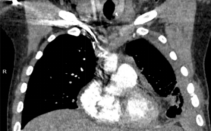

结核性胸膜炎是典型的纤维素性炎,局部纤溶活性低下,胸膜表面微血栓,凝血系统亢进,容易形成纤维蛋白的沉积和胸膜增厚。最早可发生于病程的第5天;7天就可以形成粗大的粘连带,胸腔镜下可剥离;7-30天纤维粘连逐渐增多加重,胸水逐渐减少;30天广泛粘连,难以剥离,胸腔镜难以进入。大约30%的结核性胸膜炎患者残留胸膜增厚或局限胸腔积液,50%的结核性脓胸患者需手术干预,针对伴有广泛粘连的结核性胸膜炎,局限包裹性积液和结核性脓胸,胸腔内早期注射尿激酶可降低胸腔积液的粘度,促进胸腔积液引流,减轻后期胸膜增厚的发生率。